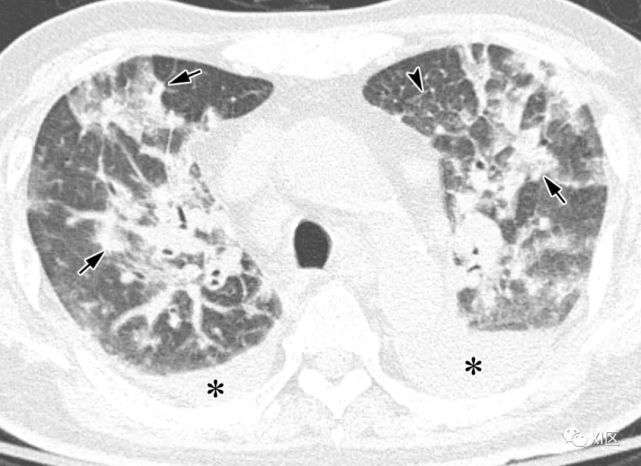

图13 63岁的男子,原发性中枢神经系统淋巴瘤化疗后合并发热,诊断为人博卡病毒肺炎

(上)胸部X线片显示两肺均弥漫性不规则斑块状实变(箭)和GGO。在同一天获得的轴位薄层(1mm)胸部CT图像显示,沿着支气管血管束和肺部周边区域出现不规则的斑块状实变(箭),支气管壁增厚,小叶间隔增厚 (箭头),伴有少量双侧胸腔积液(*)。

Koo H J , Lim S , Choe J , et al. Radiographic and CT Features of Viral Pneumonia[J]. Radiographics, 2018, 38(3):719-739.